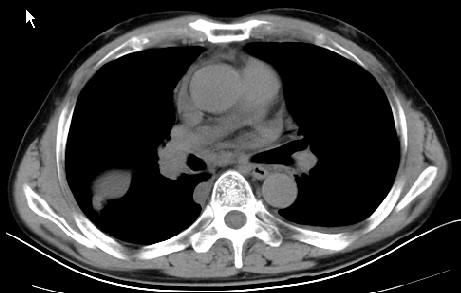

以下是引用草之原在2009-5-2 19:29:00的发言:[br]1.考虑右侧中心型肺ca纵膈淋巴结转移,双侧胸腔积液及右侧叶间裂积液,心包积液。[br]2.两肺上叶病灶,纵膈窗显示部分病灶硬化,考虑:结核。[br][br] [br]

以下是引用ct诊断高手在2009-5-2 19:08:00的发言:[br]我考虑右侧中央型肺癌 伴右肺节段性不张,两肺及纵隔淋巴结转移,右侧胸腔积液。

以下是引用zjzjr在2009-5-2 20:16:00的发言:[br]肺结核,转移瘤.纵隔淋巴结转移或淋巴瘤,右侧包裹性积液、斜裂积液。心包积液。